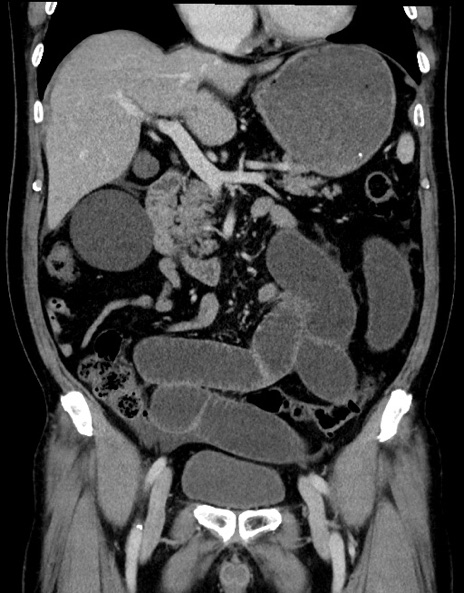

症例15(冠状断像)

【症例】70歳代男性

【主訴】腹痛

【現病歴】今朝から腹痛あり。全体的に痛い。特に左上の方。排ガスが今日はない。冷や汗が出る。

【既往歴】直腸癌術後

【身体所見】左側腹部〜上腹部に圧痛あり。腹膜刺激症状明らかなではない。軽度反跳痛。左下腹部に術後瘢痕あり。

【データ】WBC 7700、CRP 0.02